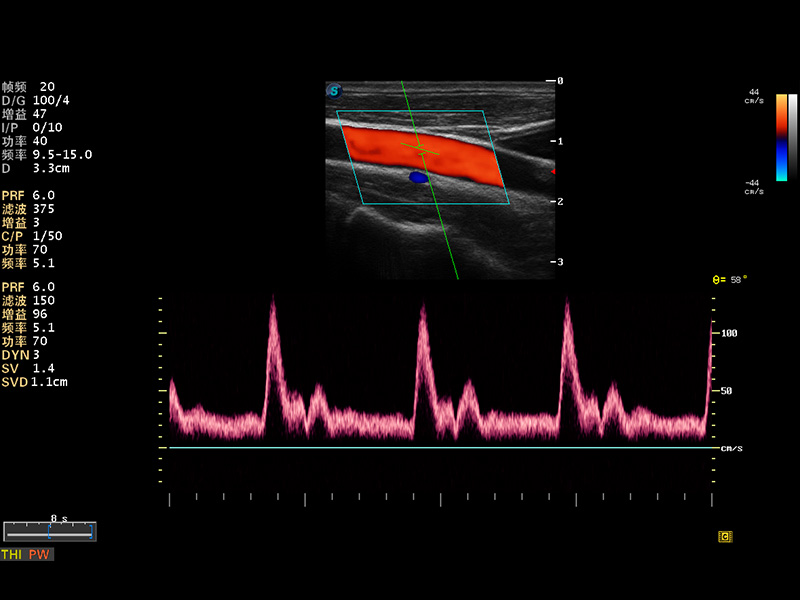

S8 EXP便攜式彩色多普勒超聲診斷儀是開立醫(yī)療研發(fā)的高端全身應(yīng)用型便攜彩超。高通道的VIS平臺(tái)融合可視化(Visual)、智能化(Intelligent)和人性化(Smart)的特點(diǎn),配以開立醫(yī)療自主研發(fā)生產(chǎn)的探頭大家族,使您能夠快速、準(zhǔn)確的獲得病人信息,提高工作效率的同時(shí)減輕疲勞。

成像技術(shù)